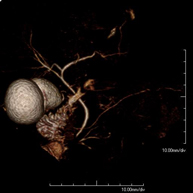

- Intracranial MRI angiography

This non-invasive diagnostic procedure uses an electromagnetic field and radio waves (from a transmitter and receiver) to acquire high-definition anatomical images of the cerebral arteries. It is a radiation-free procedure. In most cases, paramagnetic contrast (gadolinium) is required. It enables non-invasive angiographic studies using a gadolinium injection, with subsequent 2D and 3D reconstruction using specialised workstations. Indicated for: vascular malformations, cerebral artery aneurysms, arteriosclerosis.